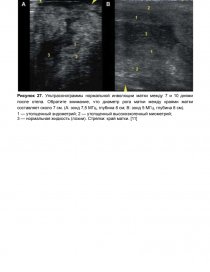

Гипофункция яичников связана с анэструсом и характеризуется отсутствием больших фолликулов без желтого тела и наличием небольших фолликулов диаметром менее 4 мм (рис. 1).

Рисунок 1. Ультразвуковое изображение гипофункции яичника (зонд 7,5 МГц, глубина 2,5 см). Обратите внимание на наличие большого количества мелких фолликулов (менее 4 мм) вокруг стромы яичника.

1 — фолликул; 2 — строма яичника [11].